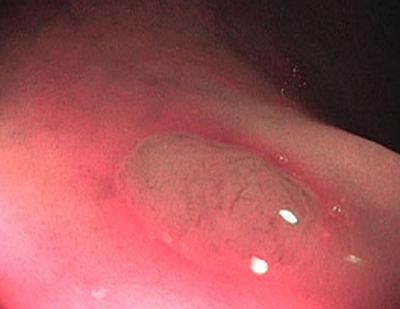

2 тип — характерний для аденоми

Колір: темніший (коричневіший), ніж навколишні

Судини: світліша ділянка в центрі, оточена більш товстими коричневими судинами

Поверхня: овальна, трубчаста, звивиста — наявність трубочок, лінійних або пучкових, світла ділянка в центрі, оточена коричневими судинами